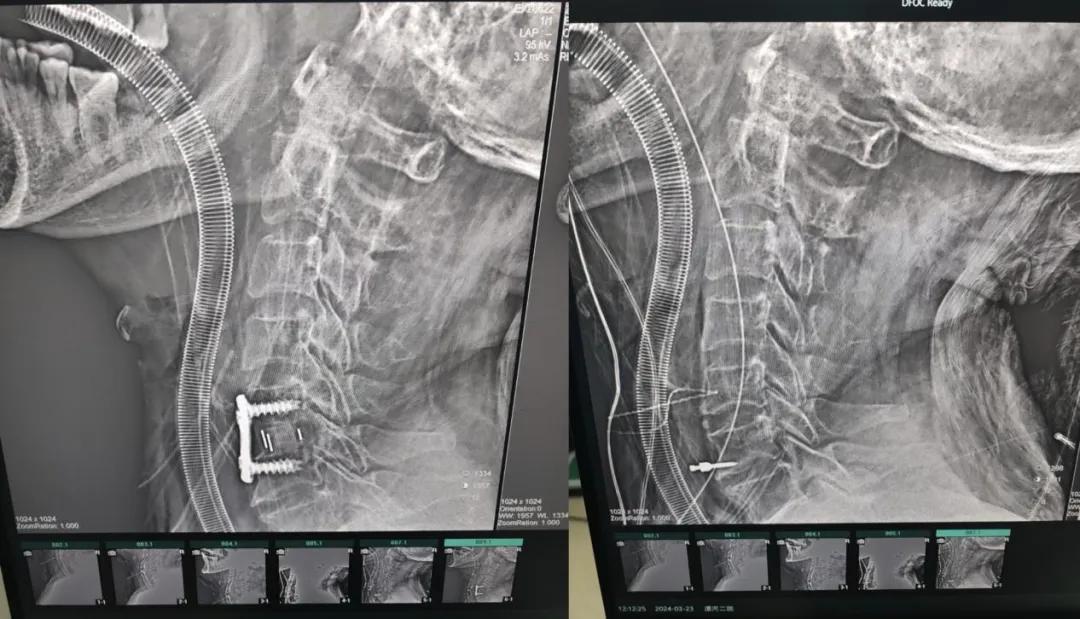

經(jīng)過縝密的術(shù)前準(zhǔn)備和手術(shù)計(jì)劃,在鄭大一附院神經(jīng)外科張風(fēng)江教授的指導(dǎo)下,神經(jīng)外科團(tuán)隊(duì)順利為患者實(shí)施“顯微鏡下頸椎前路C5/C6椎間盤切除椎間融合+內(nèi)固定術(shù)”,手術(shù)時(shí)間不到1小時(shí)。術(shù)后患者恢復(fù)情況良好。